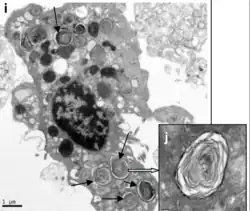

Um pneumócito é uma célula epitelial dos alvéolos pulmonares.[1] Há dois tipos de pneumócitos, os de tipo I, que constituem 40% das células e ocupam 90% da superfície do alvéolo e os de tipo II, que constituem 60% das células e ocupam apenas 10% da superfície do alvéolo.[2] [3]